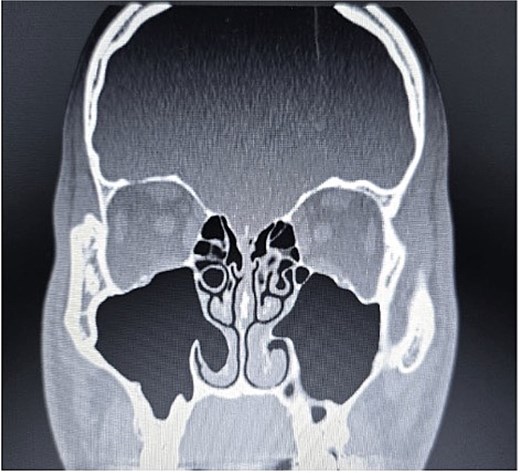

Anterior rhinoscopy and nasal endoscopy demonstrated bilateral hypertrophy of the inferior and middle turbinates, with clear and patent sinus ostia and no evidence of polyps or masses. A coronal CT scan of the paranasal sinuses revealed bilateral ICB and a unilateral CB of the left middle turbinate (Figs 3–5).

Paranasal sinus CT scan in the coronal plane demonstrating left middle concha bullosa and inferior concha bullosa.